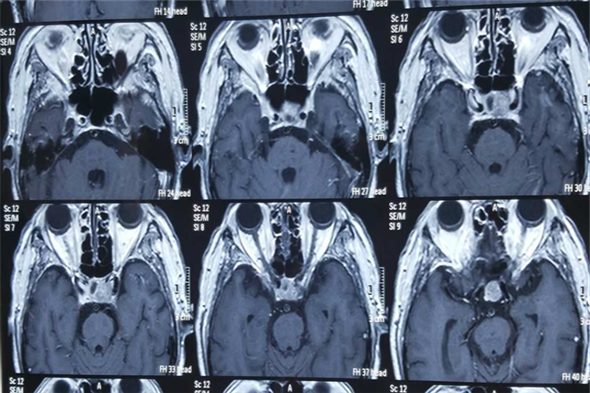

术前垂体MRI检查